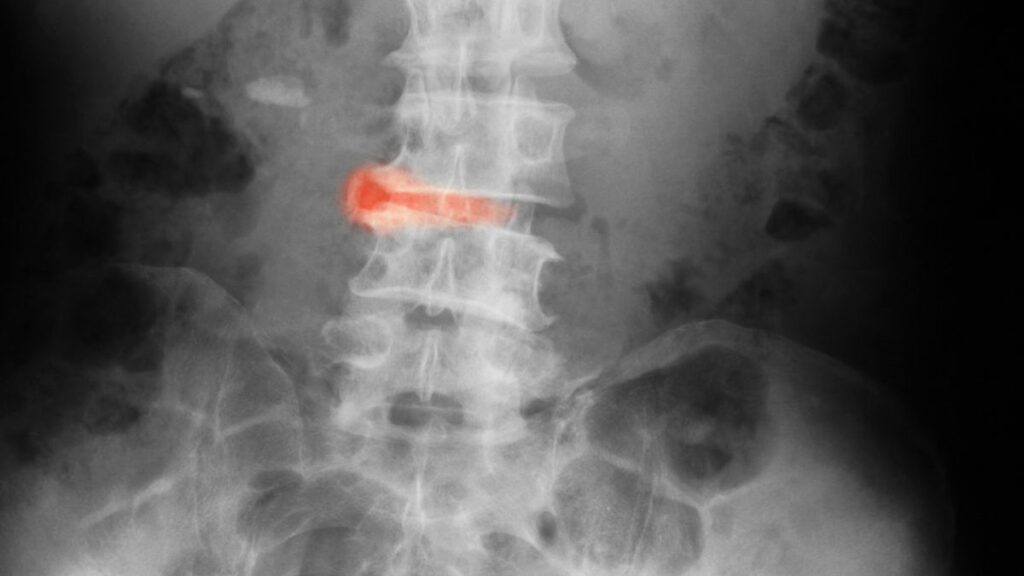

La espondilitis anquilosante (EA) es una forma de artritis autoinmune que suele afectar a la columna vertebral, las caderas o las articulaciones sacroilíacas (que conectan la columna con la pelvis), pero también a las rodillas, los tobillos, el cuello o las entesis (tejidos conectivos donde los ligamentos y los tendones se unen al hueso). Esta enfermedad provoca la inflamación de las zonas afectadas, desencadenando dolor, rigidez e hinchazón, entre otros síntomas.

Al igual que otros tipos de enfermedades inflamatorias, la espondilitis anquilosante también se caracteriza por periodos de empeoramiento de los síntomas, o brotes, y periodos de menos síntomas, más leves o inexistentes, o de remisión.